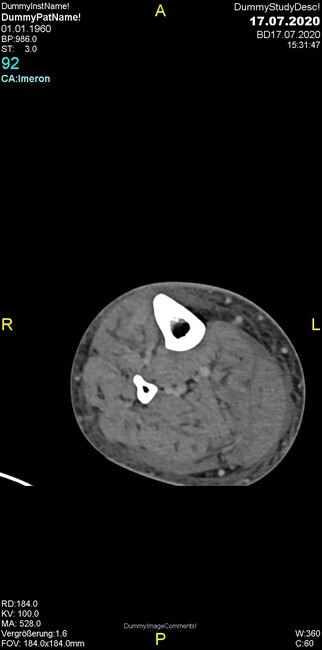

Um welche Modalitäten handelt es sich?

- Röntgen p.a. und lateral, CT coronar Knochenfenster, CT axial Weichgewebsfenster

Was fällt in der CT im Knochenfenster auf?

- Weichgewebskalzifikationen lateral angrenzend an den Gelenkspalt

- Osteolyse der Tibiametaphyse unter Beteiligung der Kortikalis

Was kommt differentialdiagnostisch in Frage?

- Osteomyelitis mit Weichgewebsanteil

- Metastase mit pathologischer Fraktur